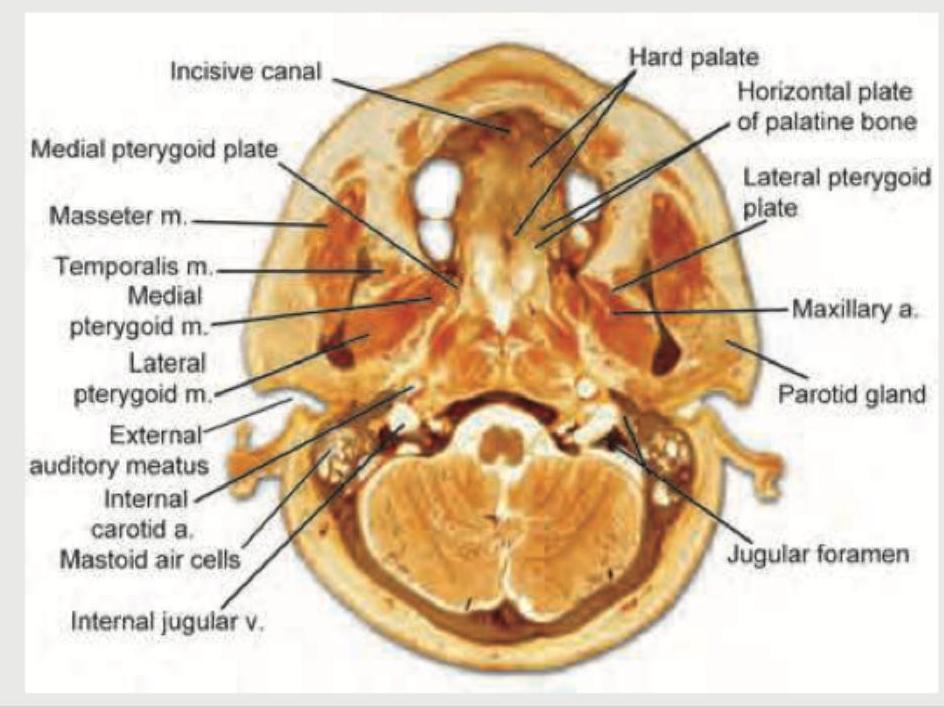

Explanation: ***Depression*** - The **lateral pterygoid muscle** is the primary muscle responsible for **depression of the mandible** (opening the mouth). - It pulls the **mandibular condyle** and articular disc anteriorly and inferiorly out of the mandibular fossa. - This action initiates mouth opening by lowering the mandible. *Elevation* - **Elevation** of the mandible (closing the mouth) is performed by the **masseter**, **temporalis**, and **medial pterygoid muscles**. - The lateral pterygoid does not contribute to elevation; it opposes this action. *Protrusion* - While the lateral pterygoid does contribute to **protrusion** (forward movement of the mandible), this is a **secondary action**. - The **primary and most important function** is depression of the mandible for mouth opening. - Bilateral contraction causes protrusion, while unilateral contraction causes lateral deviation. *Mouth closure* - **Mouth closure** involves mandibular elevation and retrusion, achieved by the **masseter**, **temporalis**, and **medial pterygoid muscles**. - The lateral pterygoid opposes mouth closure by opening the mouth and moving the mandible forward.

Temporal and Infratemporal Regions

Practice Questions